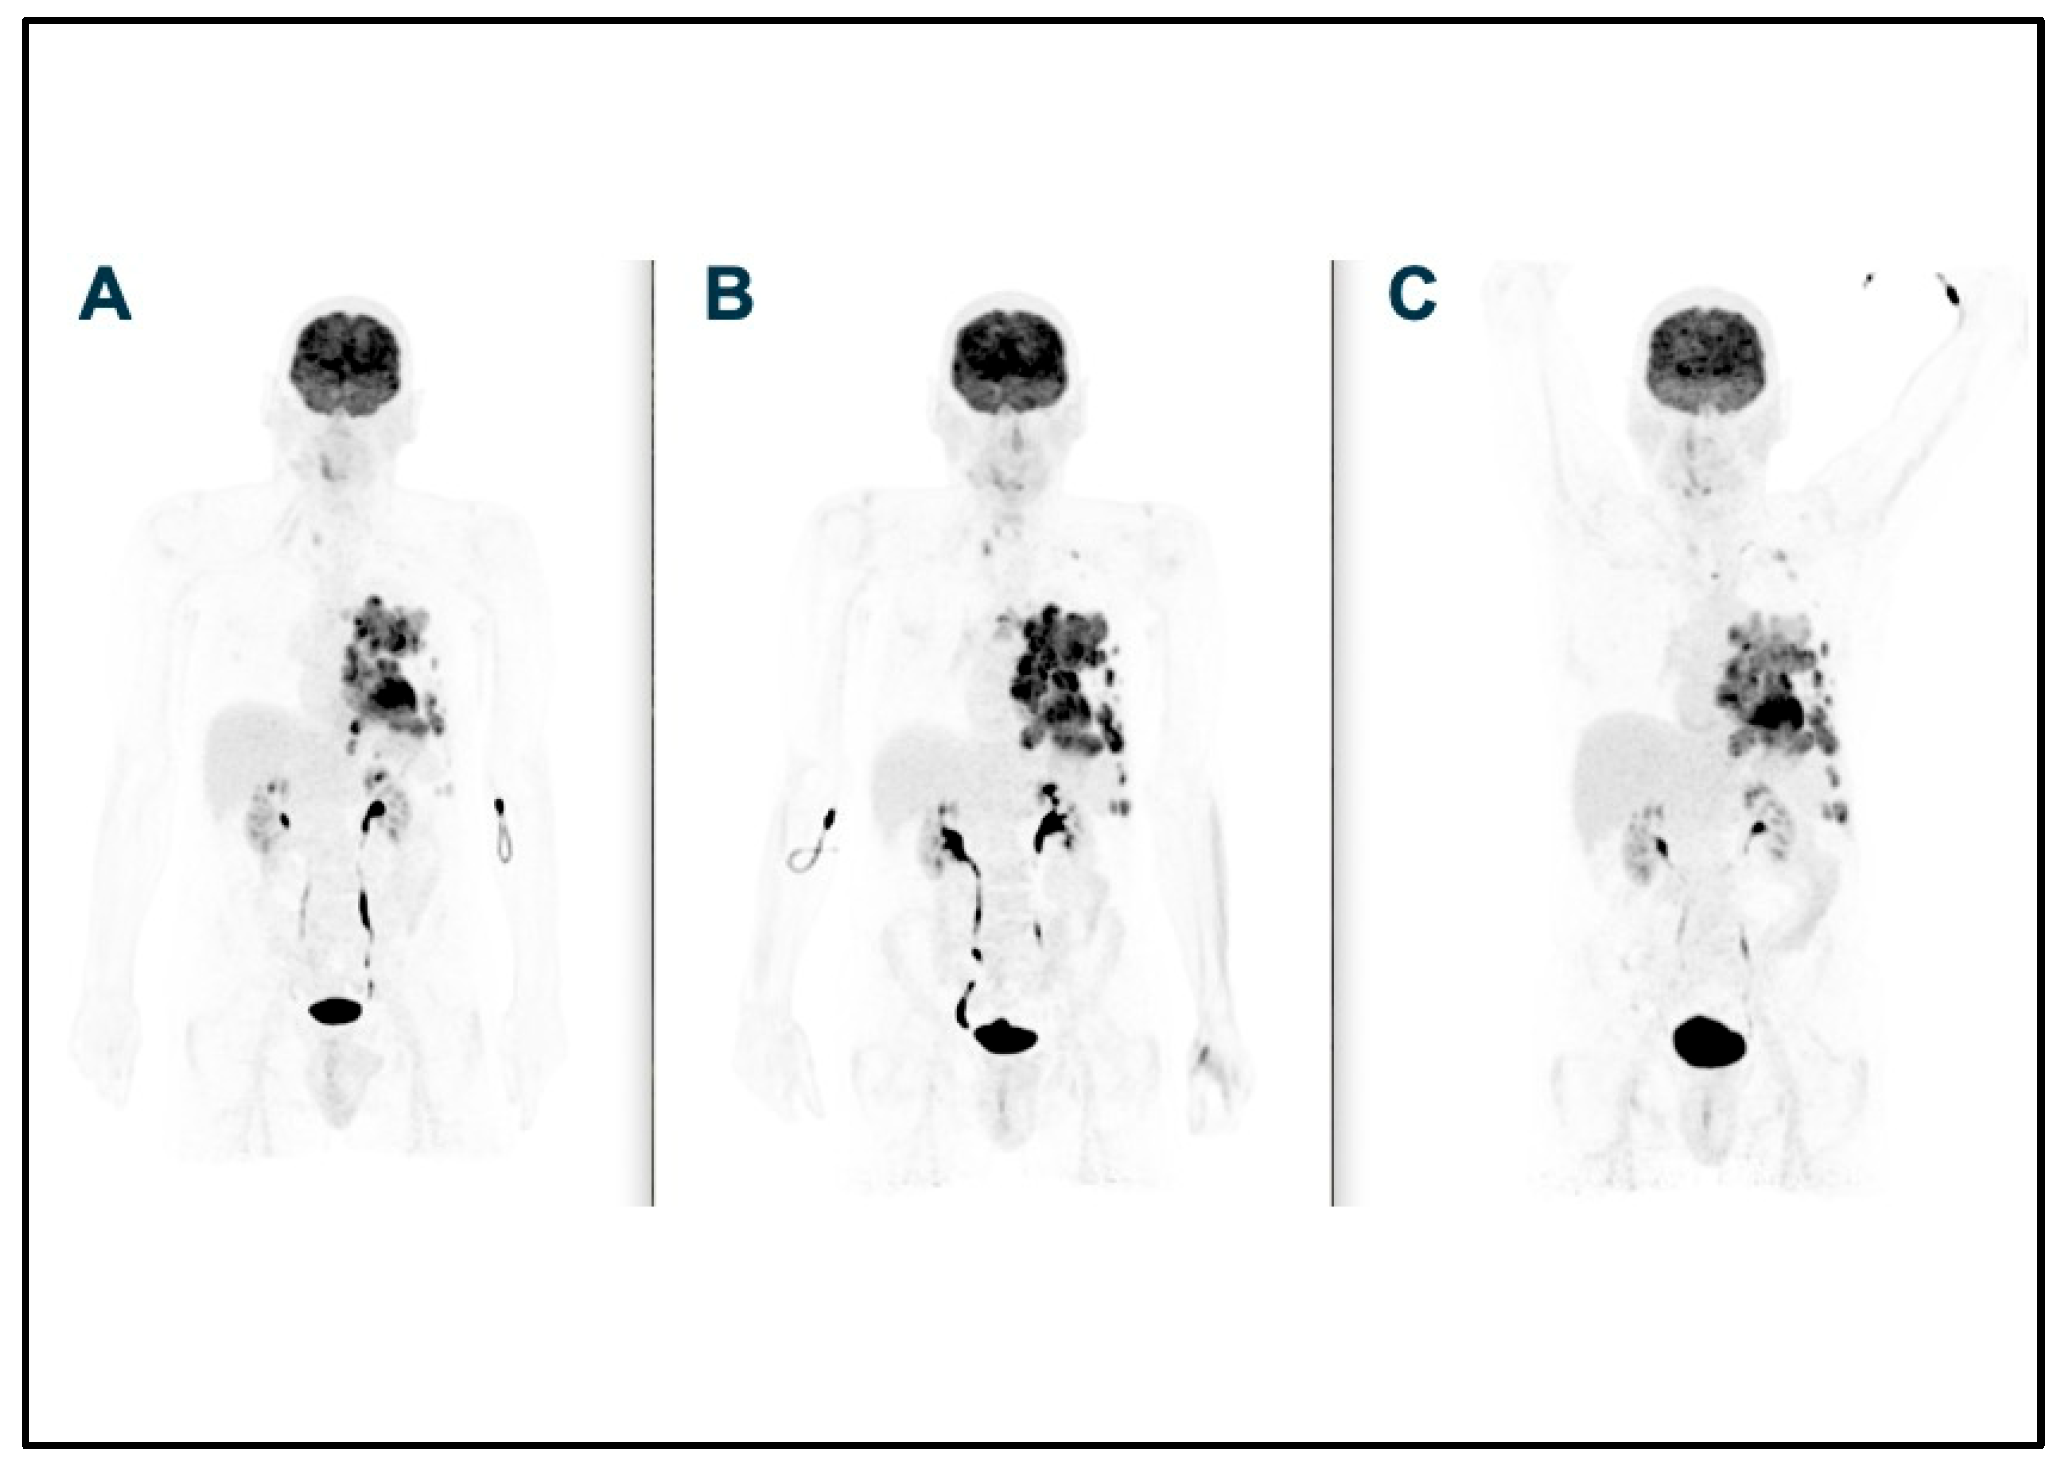

2. Case Report